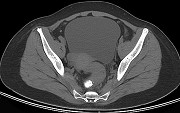

- 单项选择题男,67岁, 排便习惯改变,血便三个月入院, CT检查如图所示,下列说法错误的是  (    )

- A、直肠肠腔局限性增厚

- B、其表面欠光整,边界欠清晰

- C、可做直肠指检及活检以确定病变性质

- D、此为直肠息肉

- E、此为直肠癌